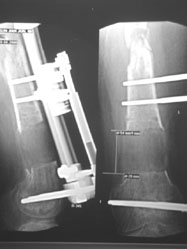

各种四肢畸形的矫正和维持等,许多严重的畸形很难通过手术一次性矫正,Ilizarov技术的缓慢拉伸提供了最佳的微创选择(图3)。区别于传统手术对畸形一次性矫正,Ilizarov技术可以对畸形进行持续不断的术后矫正,这有以下几点好处,

图3,Ilizarov环式外固定架持续纠正和维持矫形(秦泗河教授手术图片)